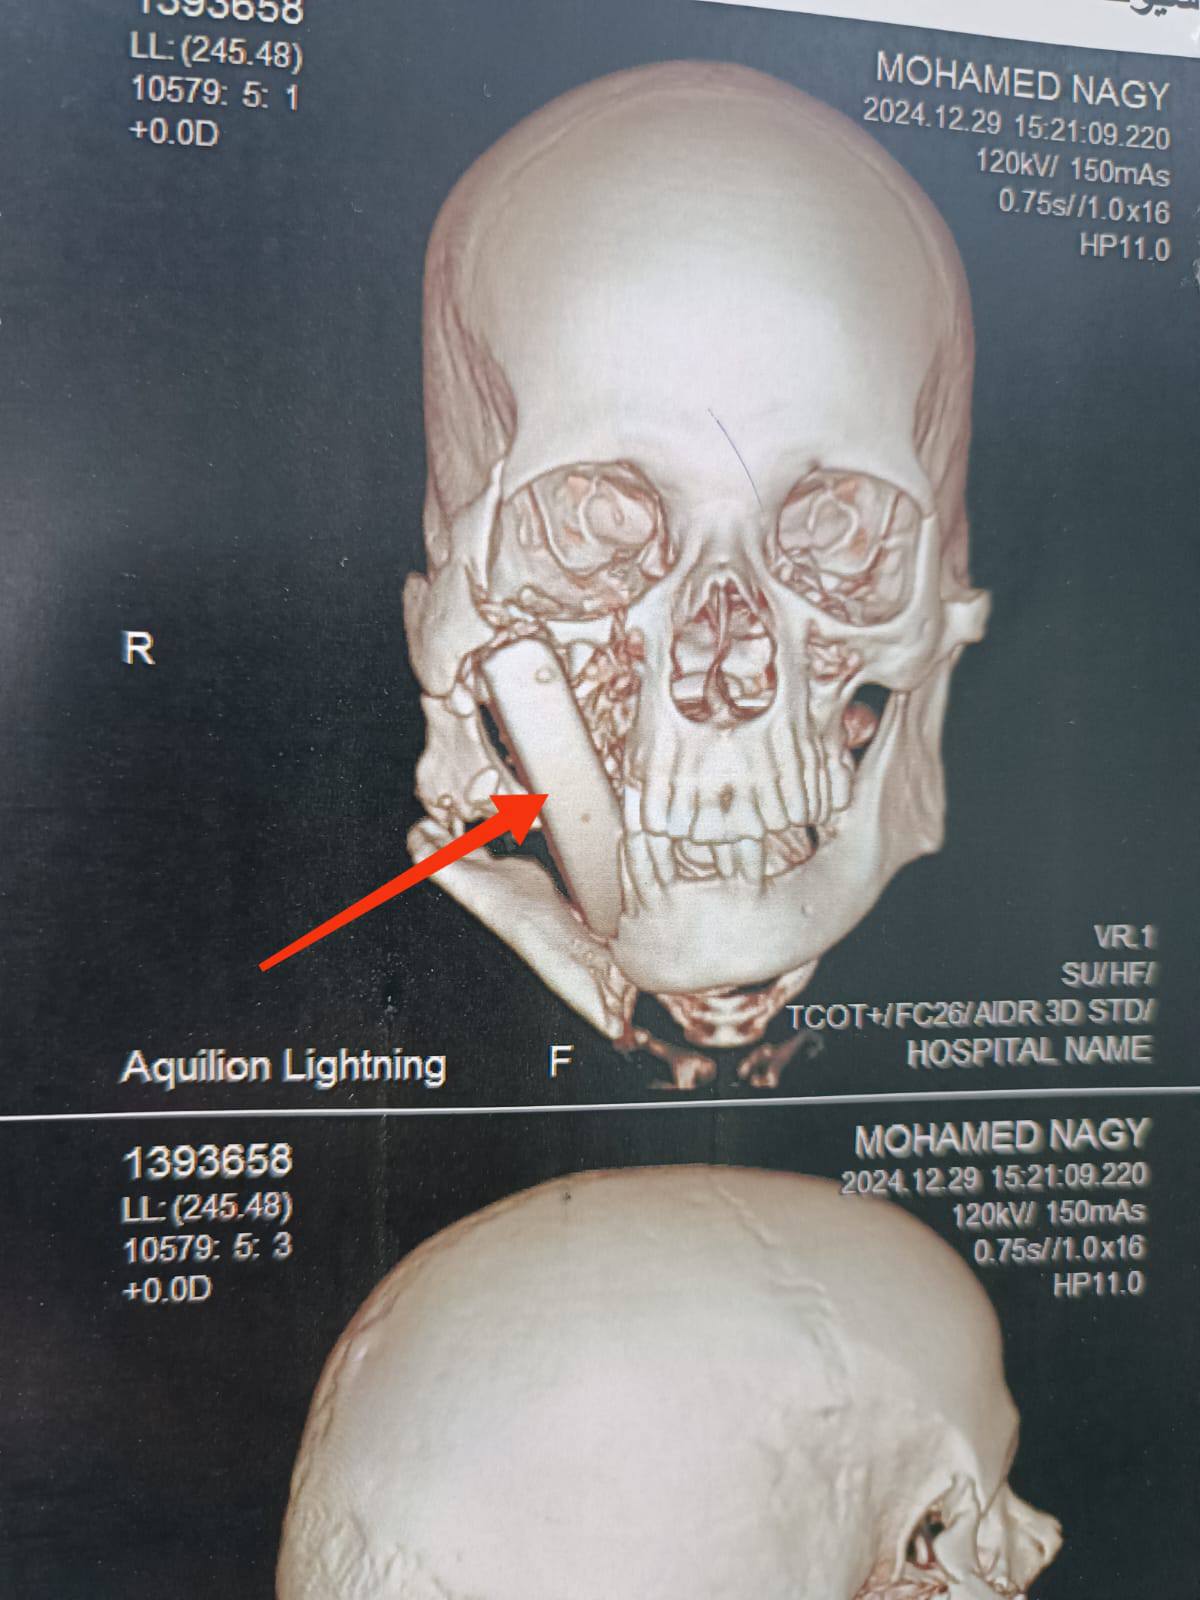

وكان مستشفى الإصابات الجامعي الجديد جامعة أسيوط، استقبل مريضًا يبلغ من العمر ٥٠ عامًا، بعد تعرضه لإصابة بالغة أثناء أداء عمله بإحدى المناطق الحجرية، والذي نتج عنه تطاير قطعة حجرية كبيرة ارتطمت بوجه المصاب، وتسببت في حدوث تهتك بأنسجة الشفاه العلوية، واستقرت داخل أنسجة الخد الأيمن، مسببةً جروح بالغة بالخد الأيمن، وقناة الغدة النكافية اليمني، وسقف الحلق والبلعوم، كما تسبب في كسور متعددة بعظام الوجنة اليمني، والفك السفلي.

وتمكّن الفريق الطبي، بوحدة جراحات الوجه والفكين والرقبة؛ من تحضير المريض والتدخل السريع، لإجراء جراحة عاجلة بعد عمل التجهيزات اللازمة، والإسعافات الأولية، ونجح الفريق في إصلاح أنسجة الخد، والفم، والبلعوم، مع استقرار الحالة الصحية للمريض بشكل جيد جدًا، ويتم تجهيز المريض لمرحلة جراحية لاحقة؛ لتثبيت كسور الوجه.